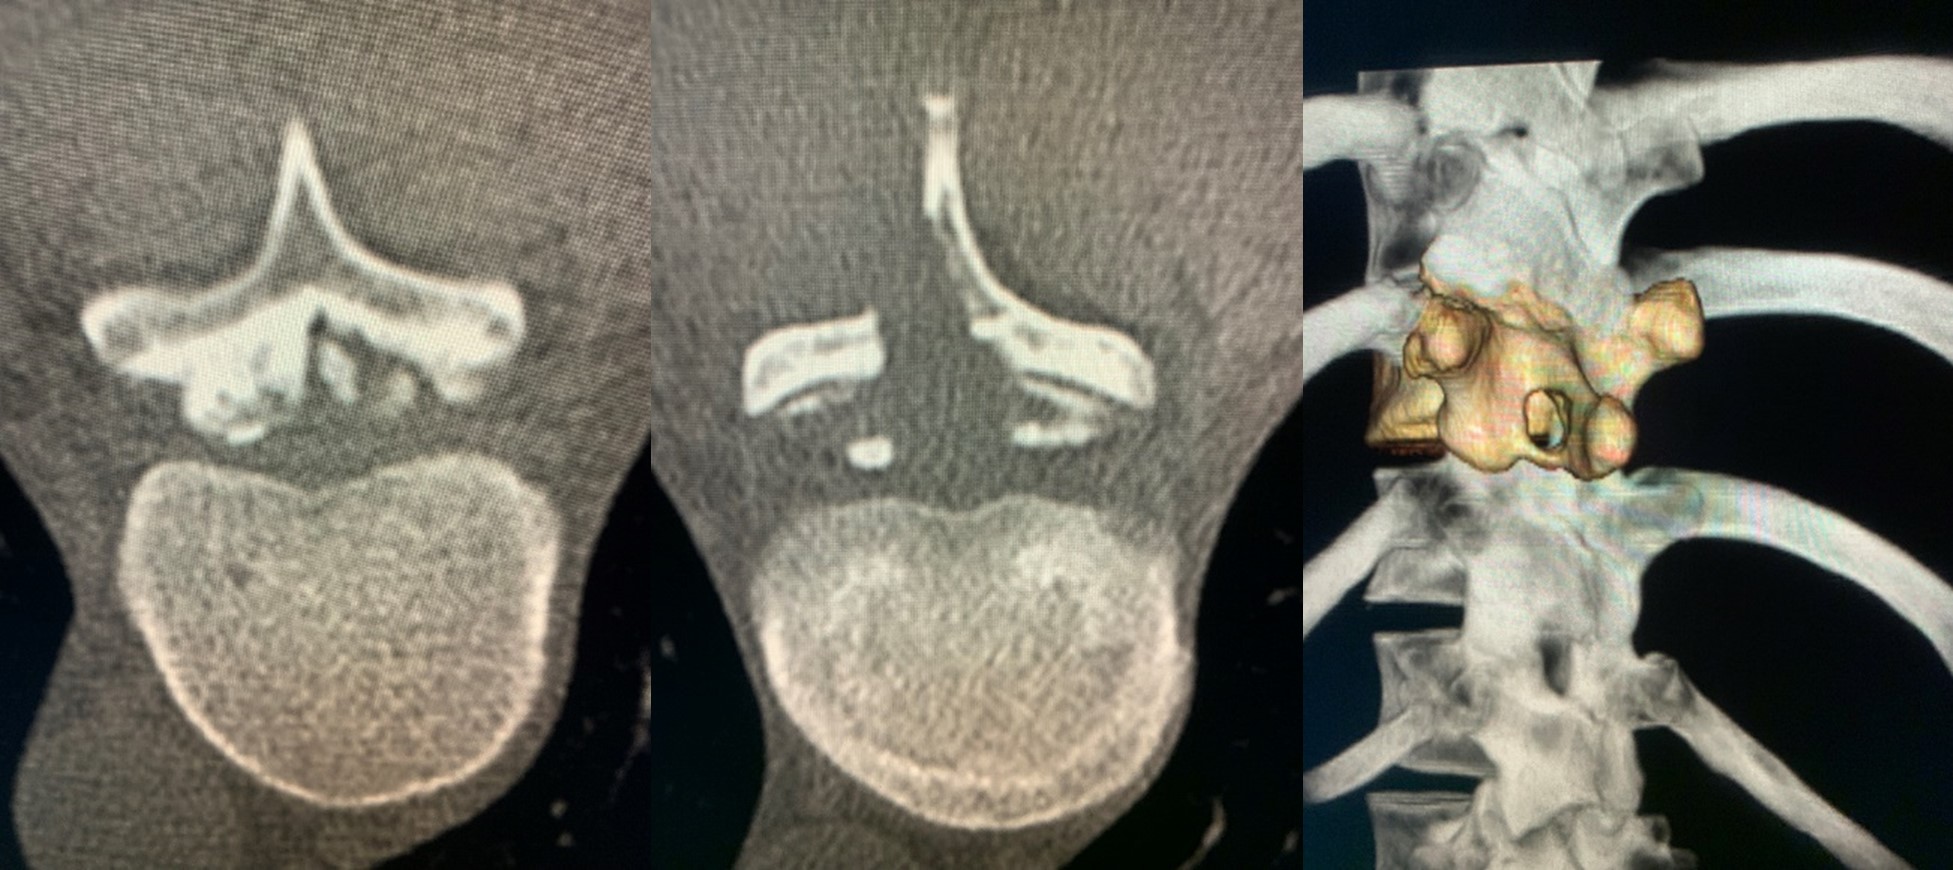

2022年に石井賢医師によって開発された難病に指定されている黄色靭帯骨化症に対する新たな手術です。黄色靭帯骨化症は脊髄が通る道(脊柱管)の中に生じます。その結果、靭帯骨化は脊髄を圧迫し、下肢の運動・感覚神経麻痺を生じます。治療は一般に背中を切って脊柱管を構成する正常な骨と靭帯骨化を切除あるいは切除しインプラントで固定する手術を行います。MISHIMA手術の場合は、ナビゲーション技術を用いて小さな皮膚切開で、正常な骨に小さな孔(マイクロウインドウ)を開けて、骨化部位のみを切除するという画期的な手術です。アスリートのみならず一般の患者さんにおいても、可能な限り正常組織を残せるという観点で素晴らしい最小侵襲治療の1つです。横浜ベイスターズの三嶋一輝投手は、2022年に胸椎黄色靭帯骨化症による下肢麻痺と排せつ障害を生じて、8月に本手術による治療を受けました。術後6週間で投球を開始し順調な回復を遂げ、2023年には開幕1軍スタートで、6月の時点で登板25、勝利3、防御率3.98という成績を残し、チームの勝利に貢献しています。本手術は、三嶋一輝投手の復活に敬意を表し、MISHIMA手術と命名されました。